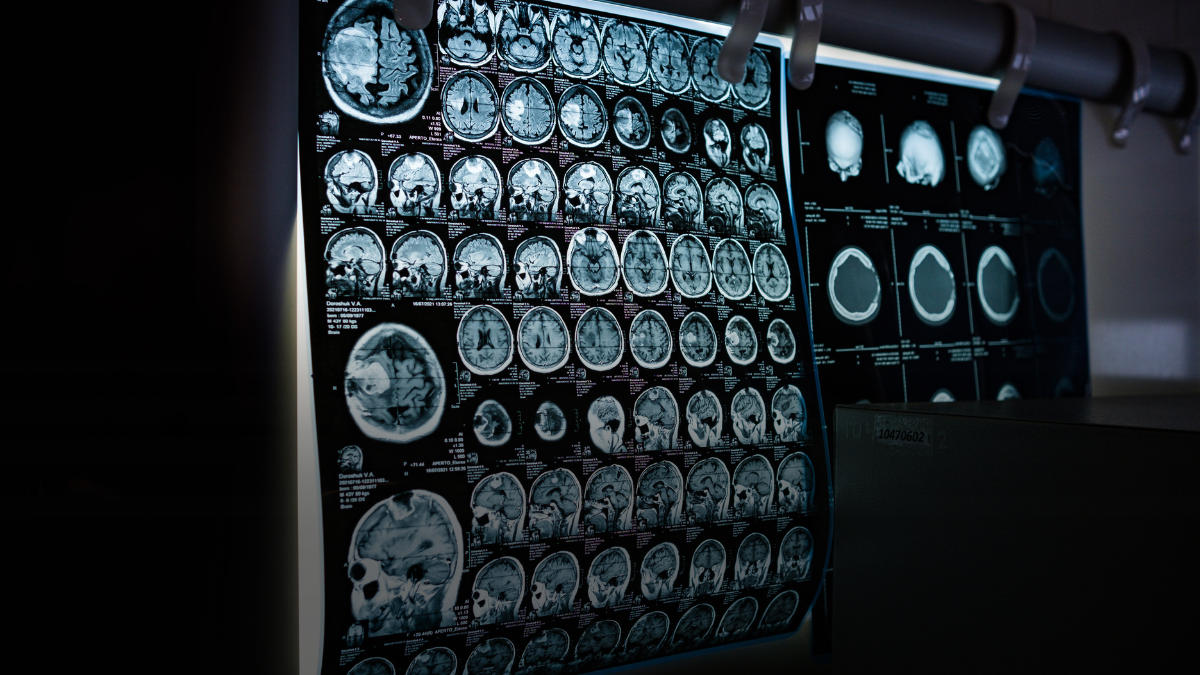

طُورت خوارزمية الكشف عن الحيوانات المموهة في الأصل لتحديد الكائنات التي تمتزج مع بيئتها بشكل يجعل اكتشافها صعباً للغاية. وفي دراسة فريدة، تم إعادة توظيف هذه الخوارزمية لتحديد أورام الدماغ باستخدام صور الرنين المغناطيسي (MRI).

- باستخدام بيانات الرنين المغناطيسي، تم تدريب الشبكة العصبية للذكاء الاصطناعي المدربة على كشف التمويه لتحديد الأورام الخبيثة في الدماغ.

- النظام يعتمد على التباينات الطفيفة بين الأنسجة السليمة والخلايا السرطانية.